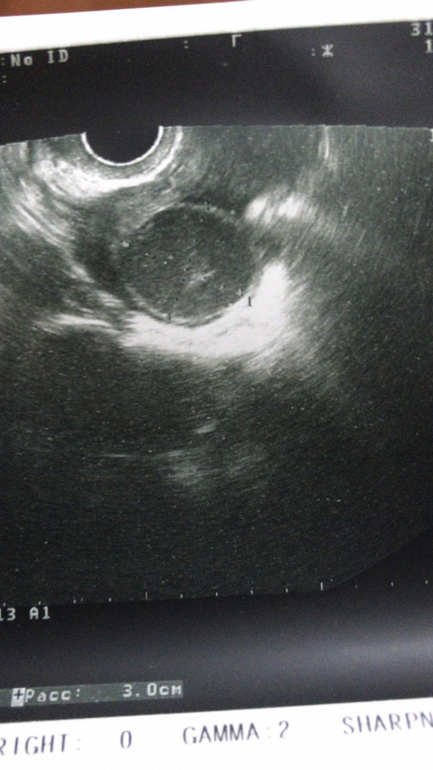

25ДЦ-ДФ нет-образование 47*40*52мм

в заключении написали киста правого яичника((

Думаю у вас фолликулярная киста, не жт. У меня в прошлом цикле была киста жт. Вот как выглядит, с М ушла. Я кучу инфы прочитала, и вроде как пока киста не уйдёт, овуляции не будет

смотрю вот,и они для меня одинаковые)шарик и шарик))

А, ну да. Я там из того, что она написала, понимаю только "округлое образование". Но в общем, киста ЖТ на узи не так выглядит - у неё края неровные и сама она мутная как будто. А когда ровная и темная - это фоллик.киста